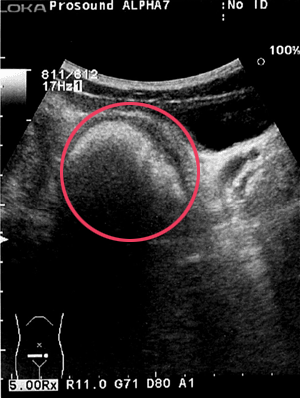

1.直腸の便塊

音響反射は強く、硬便である事が推測される。